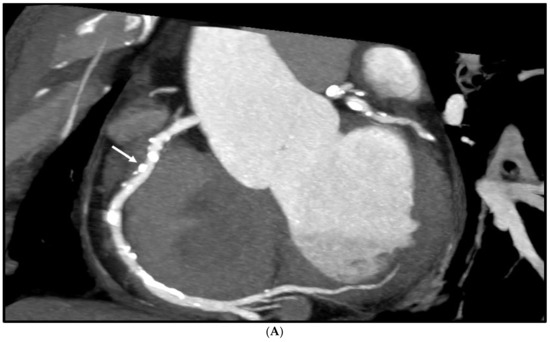

Figure 5.

Multiple calcified plaques at the right coronary artery (RCA) in a 64-year-old man with coronary artery disease. (A): Curved planar reformatted image shows multiple calcified plaques at the RCA. Arrow refers to the plaque in the proximal RCA causing >50% stenosis that was selected for comparison of lumen differences. (B): Comparison of the enhanced super-resolution generative adversarial network (ESRGAN)-processed images with original CCTA in the assessment of coronary lumen stenosis caused by the plaque (arrows) as indicated in Figure 4A. The mean lumen stenosis was measured 59%, 52%, 48% and 47% at original CCTA, ESRGAN-High Resolution (ESRGAN-HR), ESRGAN-Average (ESRGAN-A) and ESRGAN-Median (ESRGAN-M) images, respectively. (C): Invasive coronary angiography confirms no significant stenosis with measured diameter of 33% (arrow). ESRGAN-A and M images improved the lumen assessment illustrating no significant stenosis as well.